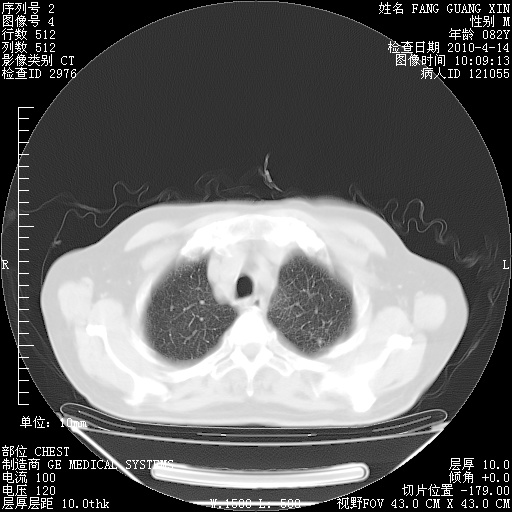

肺部CT平扫未见异常。

4月14日肺部CT